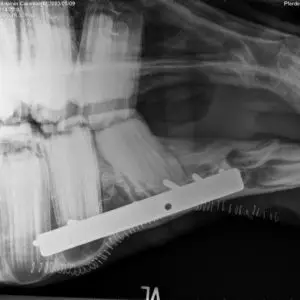

Eine Ausnahme stellen Frakturen der Elle / des Ellenbogens (Ulnafraktur) dar. Diese treten häufig bei Jungpferden auf und haben je nach Frakturverlauf eine vorsichtige bis günstige Prognose.